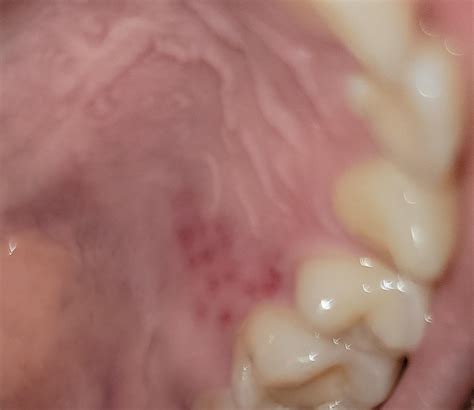

• redness on roof of mouth

• red sore spot in mouth

• rash on roof of mouth

• red spots on palate

• red sores roof of mouth

• red spots top of mouth